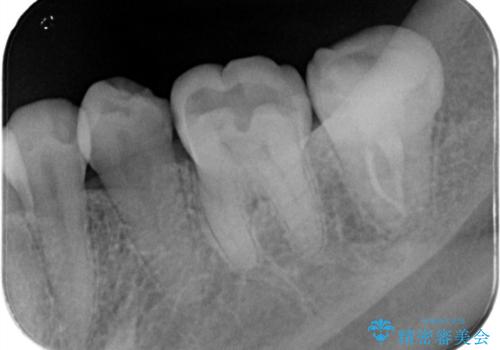

樋状根(といじょうこん)の根管治療

- 昨夜から、寝れないぐらいズキズキ痛む歯があることを主訴に来院されました。

歯髄診にて患歯を特定し、不可逆性歯髄炎の診断のもと治療を行っています。

治療中には過去に修復された材料の下に虫歯を認めましたが、破折線はみとめられませんでした。

治療後すぐに症状は改善され、今後クラウン修復を行う予定です。